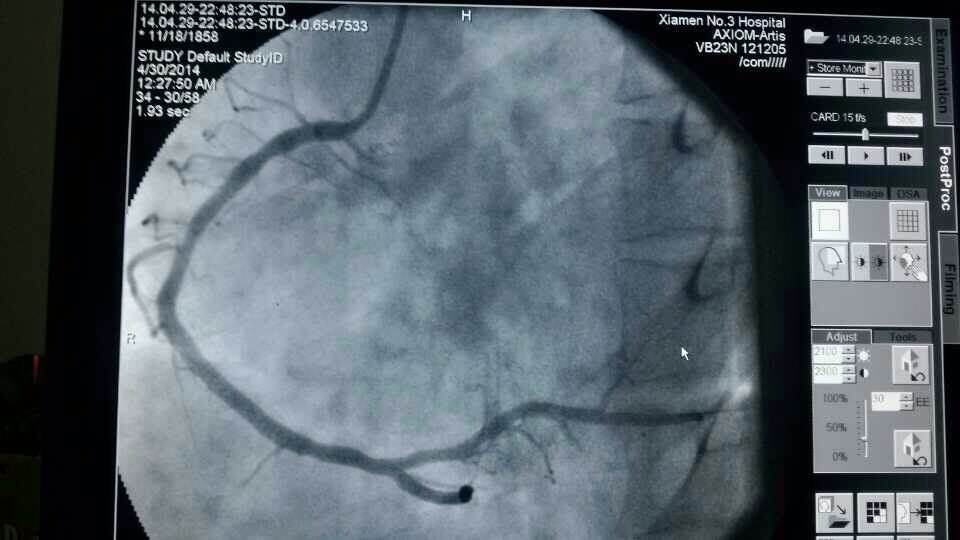

昨天仅一天的时间,厦门第三伦理片 急诊接诊9名胸痛、心梗病人,其中一名河南来厦务工的男性患者,43岁,心脏大面积心梗;另一名翔安心梗患者送到三院时已经心衰终末期,但第三伦理片 马上启动应急机制,心内科抢救技术团队第一时间到位,给予紧急打通血管,植入支架,才保住了两名患者的生命。